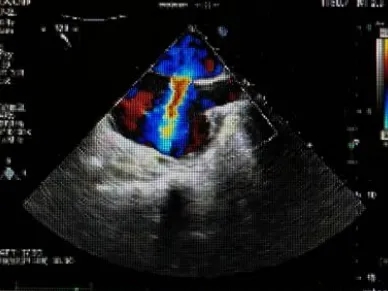

经胸超声描述:房间隔可见回声中断,胸骨旁大动脉短轴切面回声中断约14.0mm,断端与主动脉根部无明显边缘回声,心尖四腔心切面回声中断约16.8mm(除去软边),断端距二尖瓣前叶室间隔附着点约17.8mm,断端距房顶约11.7mm,房间隔全长约49.8mm,剑下双房心切面回声中断约13.3mm,剑下双房、双腔切面回声中断约12mm,房缺距上腔静脉入口较近,CDFI:房水平可见左向右分流信号。右心轻大。

超声提示:房间隔缺损(II孔型,距上腔静脉入口较近)、房水平左向右分流,右心轻大,肺动脉高压(轻度)。

主动脉短轴切面